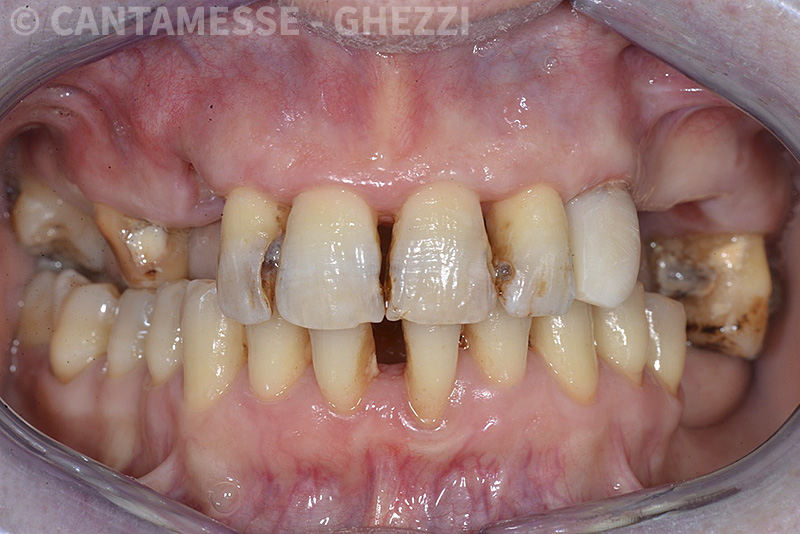

PREMESSA: in seguito all’estrazione dell’incisivo laterale superiore di destra, resasi necessaria per cause batteriche, si decide di affrontare il caso con il posizionamento di un impianto in sostituzione dell’elemento mancante dopo guarigione del sito infetto. Con tecniche rigenerative sia dei tessuti ossei mancanti a causa dell’infezione pregressa, sia dei tessuti gengivali che appaiono inizialmente troppo spostati in alto, si ripristina una corretta morfologia delle parabole (contorni) gengivali e delle papille interdentali (triangoli di gengiva tra due denti vicini).

Vengono utilizzati 2 tipi di provvisori: il primo, cementato ai denti vicini, viene utilizzato dal momento dell’estrazione del dente fino ad impianto osteointegrato (circa 6 mesi); il secondo, avvitato direttamente all’impianto, ha una funzione di prova estetica ma soprattutto di guida per la maturazione dei tessuti gengivali peri-implantari portandoli verso la maturazione completa prima di posizionare la corona finale in disilicato di litio.